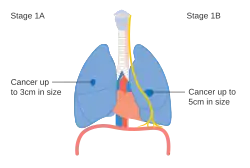

Stage IA and IB lung cancer

Stage IA and IB lung cancer -